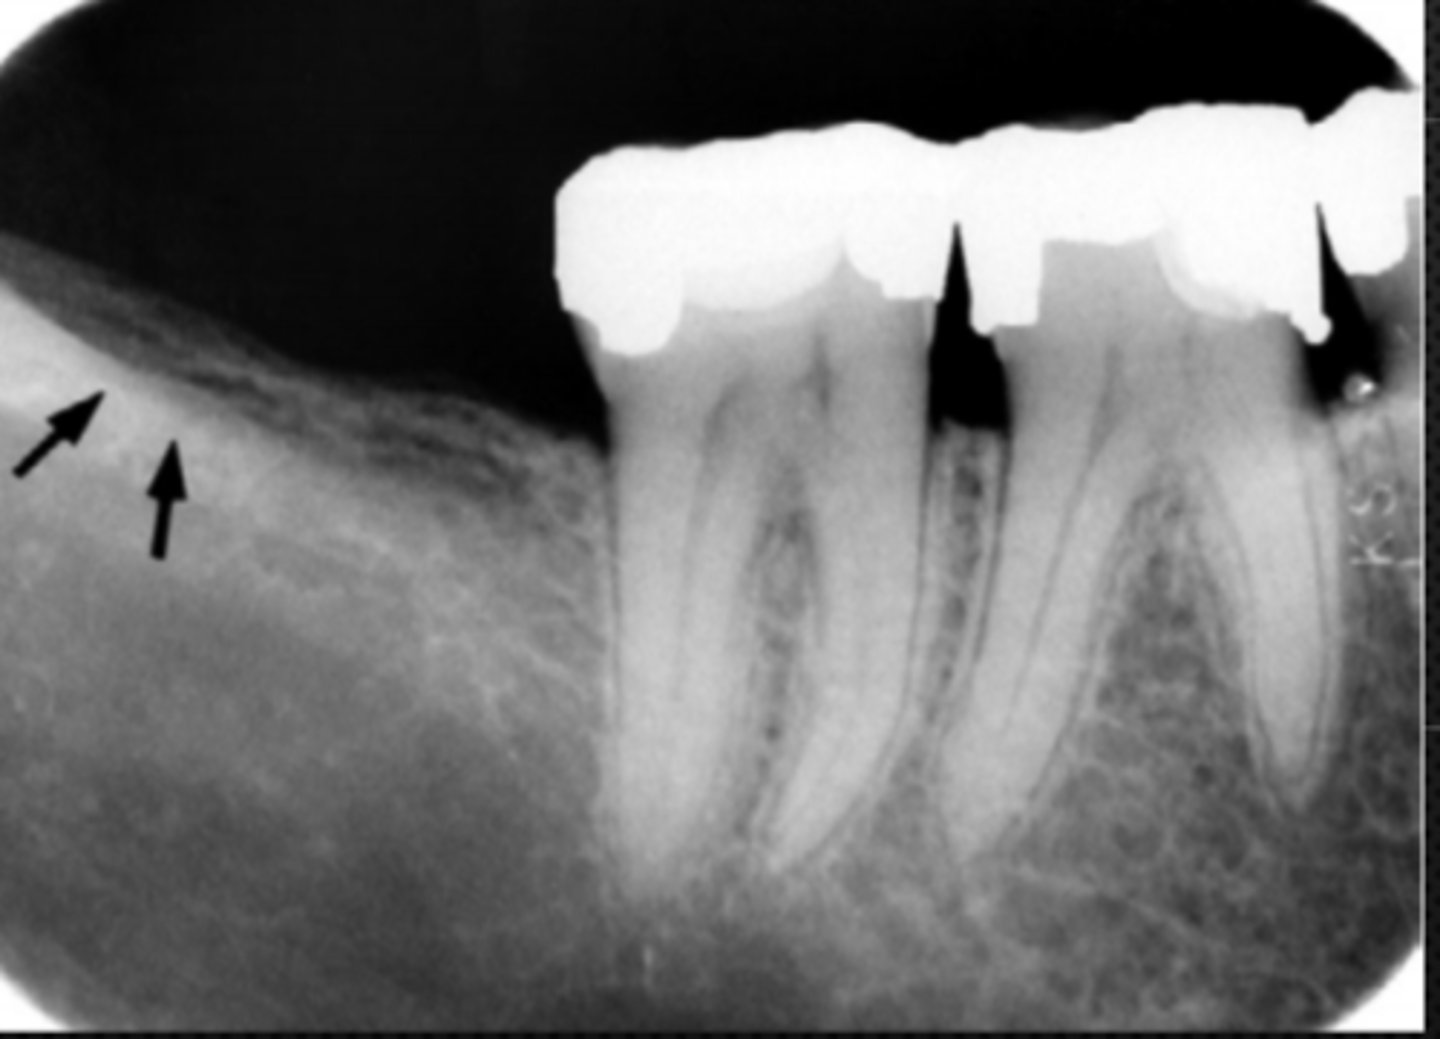

anterior border of the ramus

Name the structure the white arrow is pointing to.

<p>Name the structure the white arrow is pointing to.</p>

53

New cards

internal oblique ridge or mylohyoid ridge

Name structure the black arrow is pointing to.

<p>Name structure the black arrow is pointing to.</p>

54

Submandibular fossa

Name the radiolucent area indicated by the arrows

<p>Name the radiolucent area indicated by the arrows</p>

55